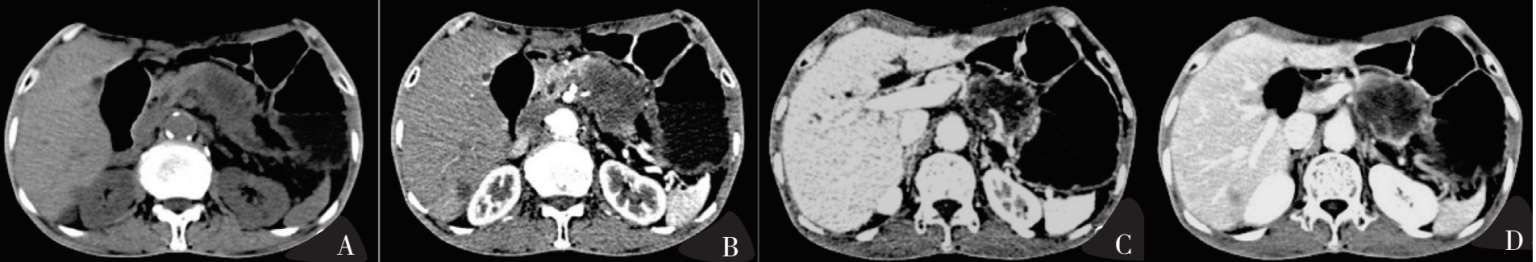

图8-2 胰腺癌影像

图8-3 胰腺癌影像,伴发肝内转移

图8-2A、图8-3A平扫期:胰体尾正常形态消失,呈局限性增大,病灶平扫呈不均匀低密度改变,边界较清楚;图8-2B:病灶强化不明显,在周围正常强化胰腺实质对比下呈不均匀低密度,胰周动脉强化,其中图8-2B显示病灶包容肠系膜上动脉及脾动脉;图8-2C门静脉期:病灶边缘呈轻度不均匀强化,与周围胰腺实质相比仍呈低强化,门静脉、肠系膜上静脉及脾静脉强化;图8-2D延迟期:病灶仍呈低强化。

图8-3显示肝内转移。图8-3A平扫期:肝内转移灶呈低密度;图8-3B动脉期:病灶中央强化不明显,边缘似呈轻度环形强化;图8-3C、图8-3D门静脉期+延迟期:肝实质明显强化,与肝内转移灶密度产生明显对比。